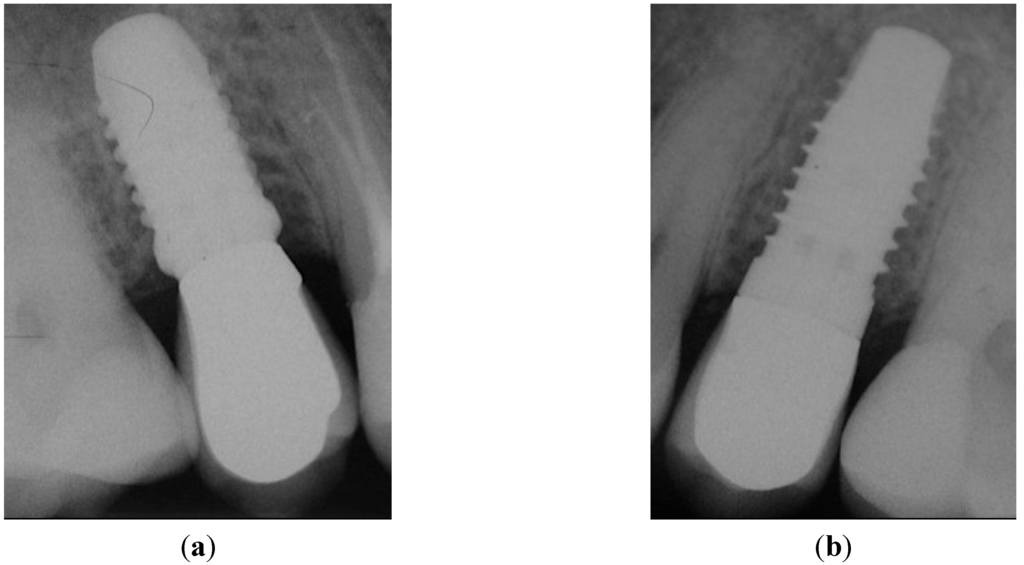

Figure 6.

Peri-apical X-rays at one-year follow-up. (a) Position 15; (b) Position 25.

The implants have been functionally loaded (AC) after six weeks. Corresponding peri-apical X-rays taken at this visit confirmed the absence of any pathological signs (Figure 5a,b; Positions 15 and 25, respectively).

Six months after study completion (at the one-year follow-up), osseointegration was checked radiographically. Both X-rays were free of any pathological signs (Figure 6a,b) with a quite satisfactory clinical outcome (Figure 7a–d). The outcome of this “split-jaw” case was equally positive for both the PFS (Position 15) and StE (Position 25) implants. In this respect, the case is representative of the entire trial patient population.